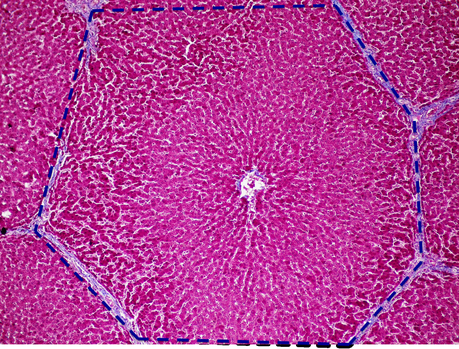

Sin abandonar la investigación con células madre realizada en nuestro país, desde el Hospital 12 de Octubre, también en Madrid, nos llega la noticia, publicada en la revista Cytotherapy, sobre la generación de hepatocitos y la posible regeneración hepática mediante el uso de células madre mesenquimales obtenidas de placenta. Un grupo multidisciplinar de científicos logra crear estructuras hepáticas funcionales –pequeños hígados de unos 5-8 cm de grosor- a partir del tipo de células señalado anteriormente y, por otro lado, consiguen ralentizar el crecimiento de ciertos tumores mamarios.

Histofisiología hepática

Las aplicaciones van en dos direcciones: por una parte el estudio permitirá, si se contrasta, la utilización de estas miniestructuras para mantener un hígado lesionado a la espera de trasplante compatible, así como la regeneración directa y eficiente de un hígado no tan lesionado como para requerir su sustitución…